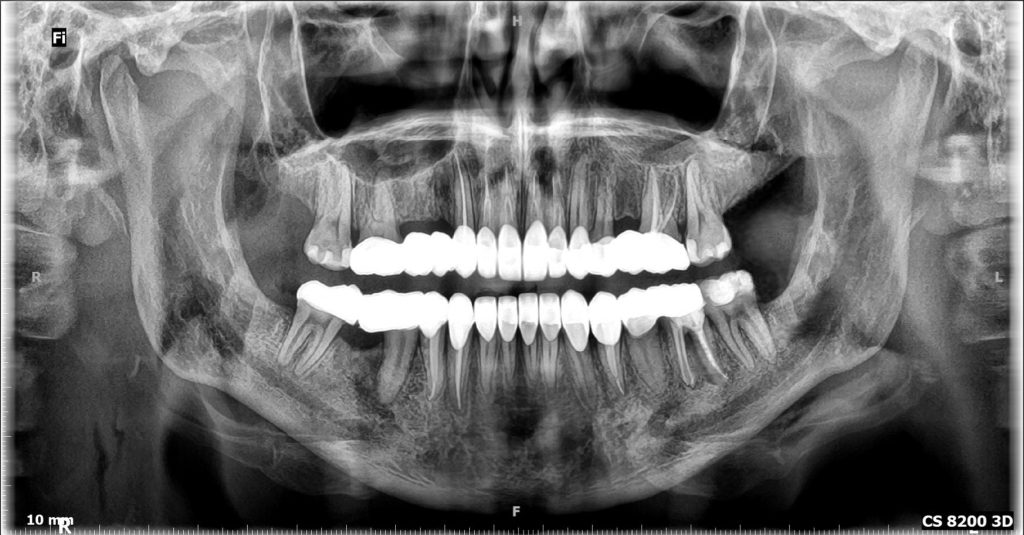

By the help of cephalometric analysis, the patient diagnosed as “Skeletal Class II”; Due to retuded mandible ( SNA= 84, SNB= 78, ANB= 5.92)

The patient suffered from Skeletal midline shift (due to improper position of the mandible) which requires invasive intentional endodontic treatment to the lower six incisors to correct the midline shift (It's better to be conservative rather than devitalization as lower midlineshift is not an esthetic concern).

More than 2 mm midline shift